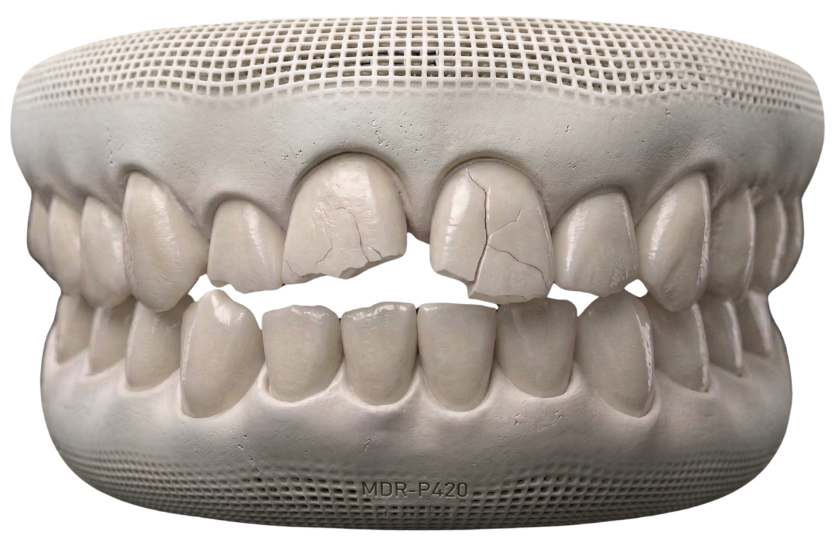

Broken or Weakened Teeth

Teeth that are cracked, worn, or heavily filled may need extra support to prevent further damage.